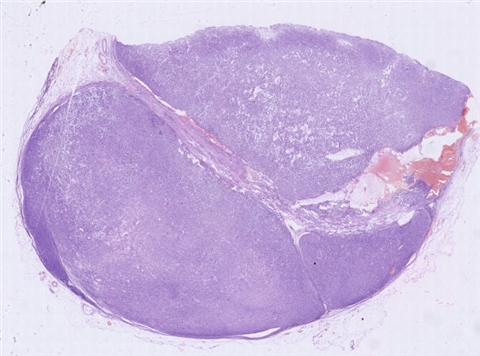

案例5 (6864)

性别:       年龄:62

患者详情: 发现双侧腹股沟肿物1月余。 查体: 双侧腹股沟可扪及多发肿大皮下肿物,大小约2*2cm,质中,边界尚清楚,活动度可,伴压痛,表面皮肤未见红肿破溃。 B超: 双侧腹股沟淋巴结肿大。 病理检查:腹股沟淋巴结穿刺活检提示淋巴组织增生。随行左侧腹股沟淋巴结切除术。

大体所见: 结节状肿物1枚,大小3×2×1.5cm,表面附有包膜,切面灰白灰红色,实性,质中。

医院: 上海长海医院